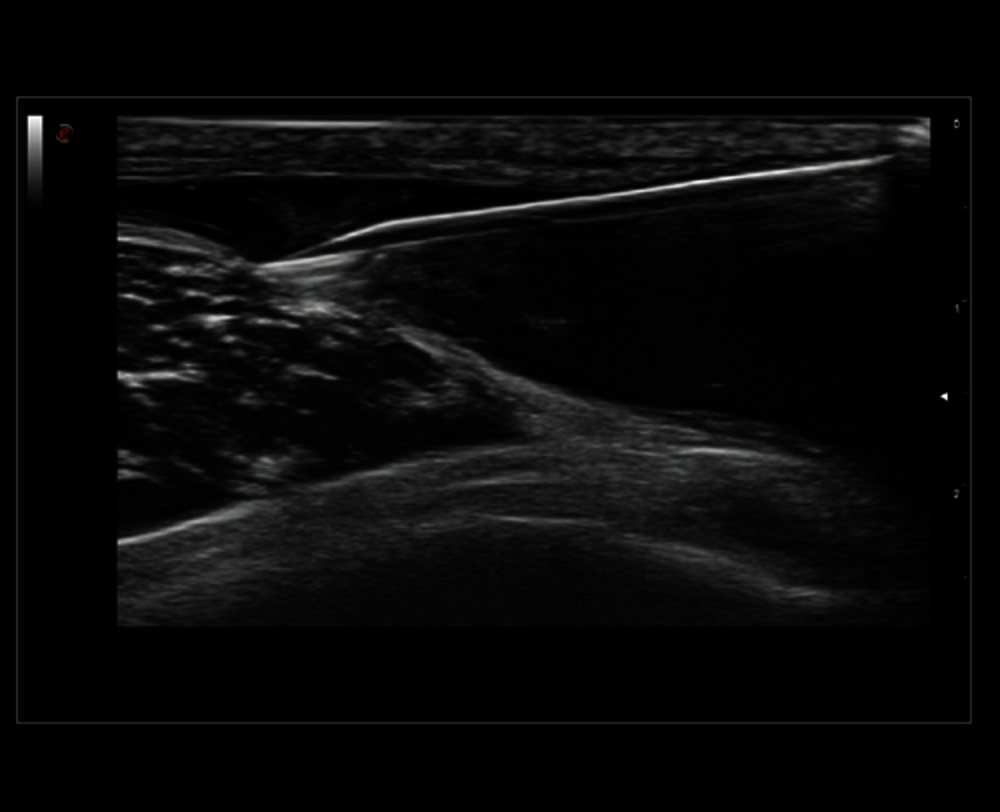

MSK zobrazení ramene